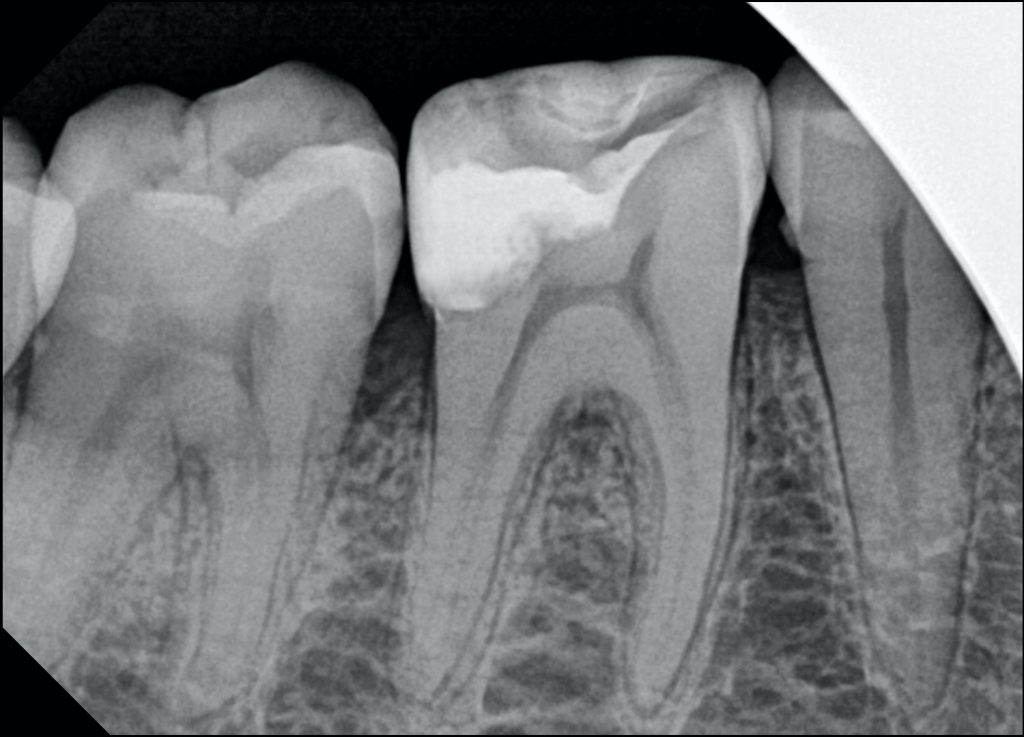

Saving vitality of LR6 (46) with Biomimetic Approach

A 34y female patient camed to our clinic complaining from food stagnation in lower right first molar with no signs of pain .. after diagnosis and sensibility test my decision was to save pulp vitality .

1-cavity optimization

-cuspal reduction